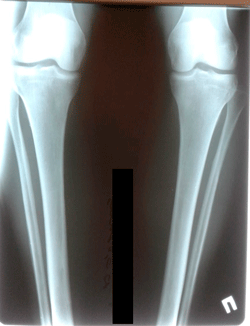

Исходник - 47 лет.

Дата операции - 11.11.2020

image-10-11-20-02-28-5.gif

image-10-11-20-02-28-2.gif

image-10-11-20-02-28-1.gif